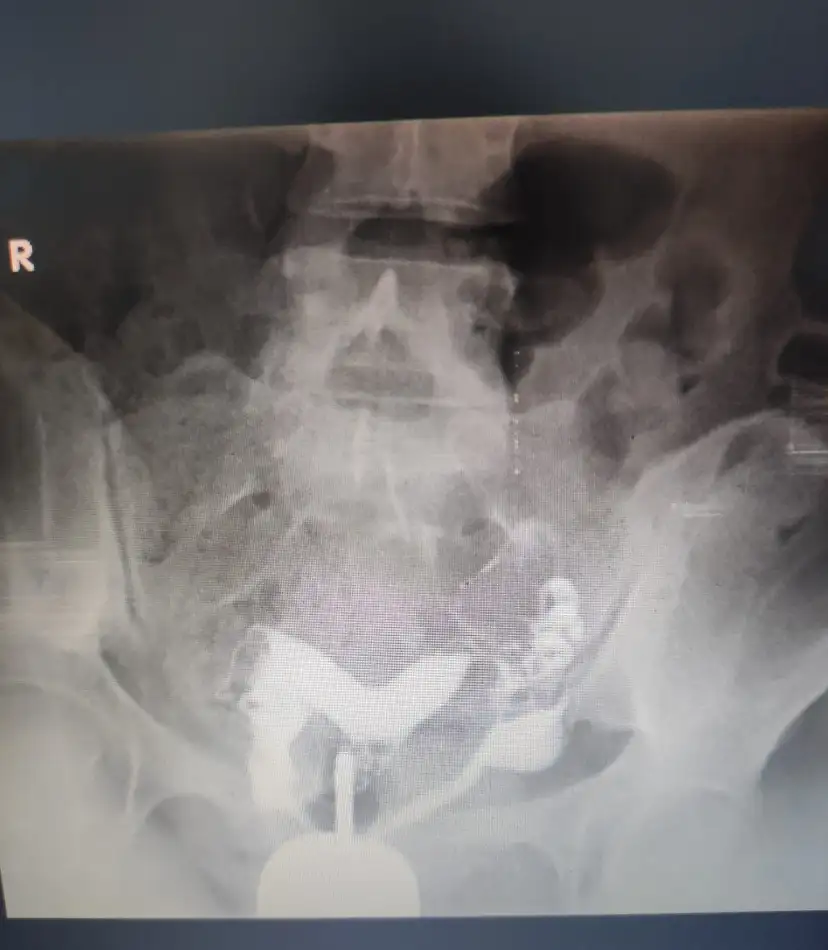

Herkese merhaba. Geçen yaz bebeğimi kalbi durması sebebiyle kaybettim. Bir hafta önce de yine diğer bebeğimin rahmimdeki perdeye tutunması ve gelişememesi sebebi ile kaybım oldu. Düşük yaptım. Rahmimde perde olduğunu ikinci kaybımda öğrendim. Ondan önce defalarca kez doktora gittim hatta rahim filmi bile çektirdim. Kalp şeklinde senin rahmin gebe kal bekliyoruz dediler. Çok doktor gezdim. Şimdiki düşüğümde takibimi yapan doktor size üzülüyorum tanı koyamıyorlar kapı kapı geziyorsunuz dedi. Ama kader gerçekten on doktora da gitsen yaşanacak varsa yaşanıyor. Her neyse düşüğümü yapalı bir hafta oldu. Doktor ilk adetinden sonra haberleşelim perdeyi almam lazım dedi. Histeroskopi olacağım. Ancak iki kere ameliyat etmem gerekebilir perden epey derin dedi. Hiç iki kere ameliyat olanınız oldu mu? Akıl almak istiyorum. Korkuyorum. Rahmin delinmesi ihtimali beni çok korkutuyor. Hele ki ikinci ameliyat olmam gerekirse .. düşükten sonra ameliyat için bir ay bekle, ameliyat ol üç ay rahmin dinlenmesini bekle, kontrole git hala perde varsa tekrar ameliyat ol üç ay daha bekle sonra doktor izniyle gebelik dene derken .. çok yoruldum ya çok yoruldumDesteklerinize ihtiyacım var. Rahim filmi görselini de ekliyorum. Bu ameliyatı olup güzel hamilelik geçirenler lütfen paylaşsın benimle. Moral toplamam lazım lütfen